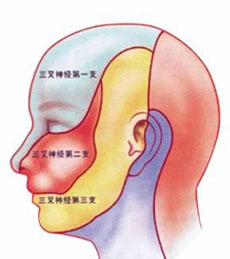

带状疱疹病毒性睑皮炎

疾病介绍:本病是由带状疱疹病毒感染三叉神经半月神经节或三叉神经第一支所致,多见于老年人或体弱者。多有发热、乏力、全身不适的前驱症状。随后病变区出现剧烈…【详细】